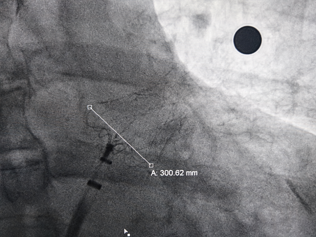

术中DSA左心耳造影+测量确认心耳形态和位置

右肩位左心耳造影

肝位左心耳造影

DSA左心耳造影

(正足位造影)

肝位左心耳测量,开口26mm,上叶深度32mm